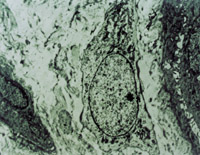

伤后12h急诊入院,检查双下肢为浅Ⅲ度烧伤。创面表皮已坏死剥脱,真皮层变性坏死呈蜡黄色和蜡白色相间(图5-3-1)。取局部组织做病理切片检查,显示上皮组织全层坏死,真皮层胶原纤维变性,结构紊乱,微循环瘀滞(图5-3-2)。

5-3-2 上皮组织全层坏死,胶原纤维变性,微循环瘀滞 HE×20